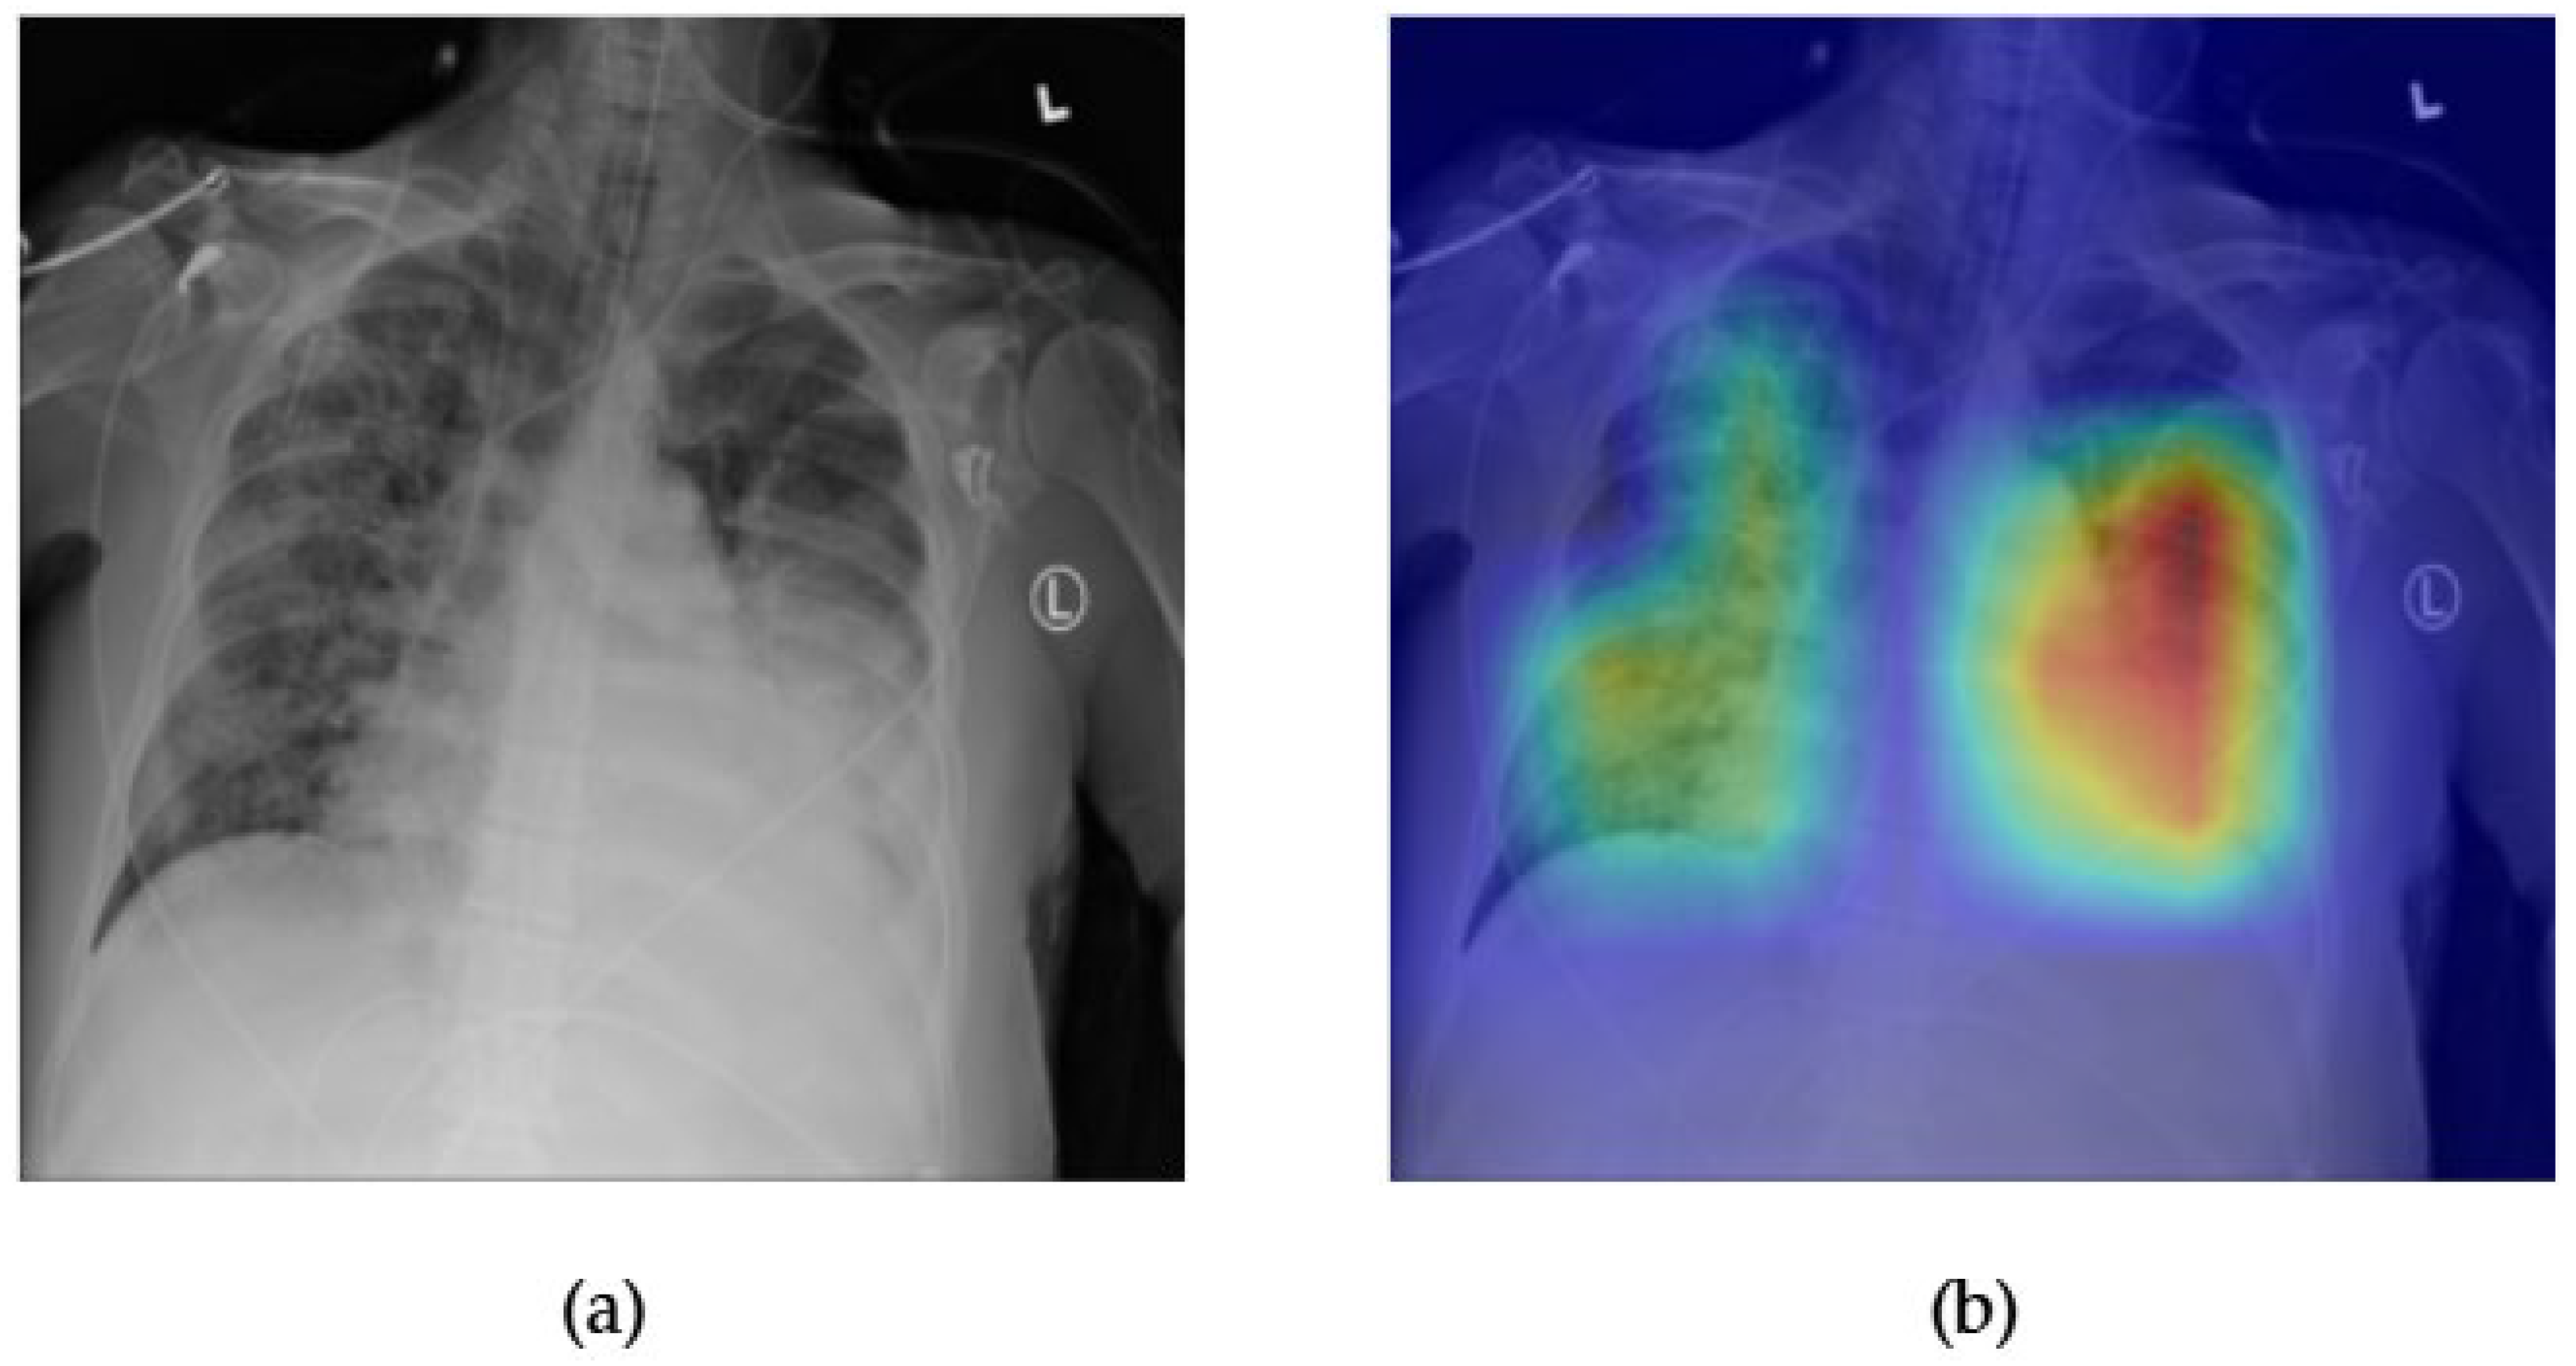

- Although our Grad-CAM-based explainability provides useful localization cues, it is inherently limited by its post hoc nature and reliance on gradient flow from the final convolutional layers. Future research could incorporate advanced interpretability techniques such as Layer-wise Relevance Propagation (LRP), Integrated Gradients, or attention rollouts in Transformers, which may offer a more complete understanding of model reasoning.